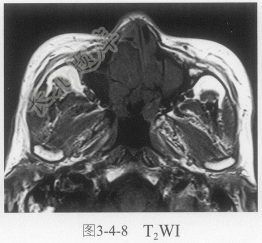

- 单项选择题4.进一步鼻窦MRI平扫及增强扫描见图3-4-7~图3-4-9。肿块信号特点是:

A、软组织肿块T

WI等稍高信号,T2WI为等低信号,增强扫描强化明显B、软组织肿块T

WI等信号,T2WI等信号,增强扫描无明显强化C、肿块多中心多发

D、鼻窦黏膜增厚,提示慢性炎症恶变

E、肿块没有什么特点